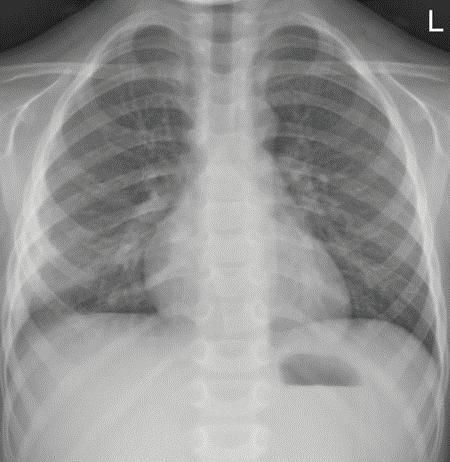

Придобитата в обществото пнев мония (ППО) все още остава чес та причина за заболяемост и смърт ност в световен мащаб. Честотата е най-висока при деца на възраст под 5 години и е от 10 до 40 случая на 1000 деца годишно[1,2]. Изчислено е, че ППО е причина за една пета от смъртните случаи при малки деца, с около два милиона смъртни случая годишно в развиващите се страни и развитият свят.

В световен мащаб S. pneumoniae и H. influenzae са водещите причинители на бактериална пневмония. Най-чес тите патогени, идентифицирани при последното активно наблюдение на населението в Съединените щати, са човешки риновирус, грипен вирус и Streptococcus pneumoniae[4]. Метицилин-резистентен Staphylococcus aureus (MRSA), който първоначално е определян като но зокомиален патоген, все по-често се открива

ност [СПИН] и тежка съпътстваща бе лодробна болест, като бронхиекта зии, кистична фиброза и хронична обструктивна белодробна болест [ХОББ])[8]. Известно е (главно на база та на проучвания на пунктати от бе лите дробове, проведени в развива щите се страни), че леката и умерена ППО се причинява главно от вируси, особено през първите години от жи вота, докато повечето случаи на теж ка ППО се причиняват от бактерии. Въпреки това е доказано, че грипни те вируси и респираторно-синцити алният вирус играят

в общността, където се на рича придобит в общността MRSA. Същият може да доведе до тежки бе лодробни инфекции, включително некротизираща и хеморагична пнев мония[7] Инфекцията с Pseudomonas aeruginosa е рядка при липса на спе цифични рискови фактори (скорош но антибиотично лечение, синдром на придобита имунна недостатъч

основна роля в причиняването на тежка и/или ус ложнена ППО. Значителен брой деца с ППО, причинени от атипични бак терии, показват сложно протичане, поради наличието на плеврален из лив[5] РИСКОВИ ФАКТОРИ И ЗАЩИТНИ МЕХАНИЗМИ НА ОРГАНИЗМА Микроорганизмите са разви ли разнообразни механизми, кои то благоприятстват колонизация та им в гостоприемника. Например, Парапневмонични усложнения – случаи от практиката Ю. Димитрова, Д. Хасанова, И. Цочева Отделение по педи атрия, УМБАЛСМ “Н. И. Пирогов” - София Придобитата в обществото пневмония все още остава честа причина за заболяемост и смърт ност в световен мащаб. Честотата е най-висока при деца под 5 години. S. pneumoniae и H. influenzae са водещите причинители на бактериална пневмония. При деца над 5-годиш на възраст зачестяват атипичните бактериални причинители - Mycoplasma pneumoniae и Chlamydophila pneumoniaе. Най-често тежките пневмонии, които протичат с усложнения, са вследствие на бактериални причинители и се изявяват с парапневмоничен излив, емпиема, мултилобарно заболяване, кавитарен абсцес, некротизираща пневмония, пневмоторакс, и бронхоплеврална фистула. ПЕДИАТРИЯ Ключови думи: Деца, ППО, парапневмонични усложнения.